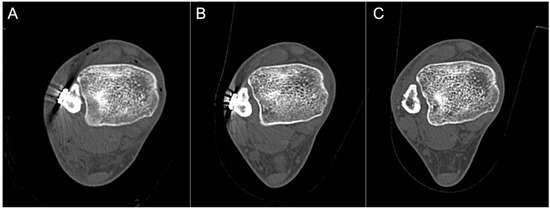

2.6. Computed Tomography (CT) Analysis